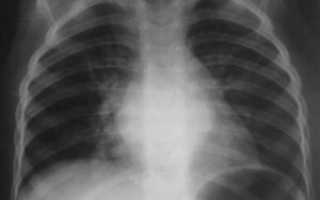

классический вариант бронхита на рентген-снимкепневмония на рентген-снимке: видно почти полное затемнение нижней доли

Несмотря на некоторые различия пневмонии и бронхита, нередко клиника бывает размытой.

В такой ситуации для установления верного диагноза необходимо сделать флюорографию или рентгенографию – это наиболее достоверный способ диагностики. По результатам рентгенограммы лечащий врач сможет легко распознать болезнь.

Худшие опасения подтвердятся, если на снимке будут отчётливые затемнения.

Первый признак пневмонии на рентгеновском снимке – появление очагов затемнения с неровными контурами в разных частях легкого, которые могут иметь разный размер, от 3-4-х до 12 мм.

Тени различают по внешнему виду (круглые, овальные кольцевидные) и интенсивности окраски – чем темнее пятно, тем сильнее выражен патологический процесс.

При поражении лимфатических узлов и нарушении кровоснабжения органа могут наблюдаться изменения корней легких, а если болезнь затронула плевру – нарушение в рисунке куполов диафрагмы. В остальном проявления пневмонии зависят от стадии, формы и клинических особенностей заболевания:

| Рентген | Усиление лёгочного рисунка | Очаговые затемнения |